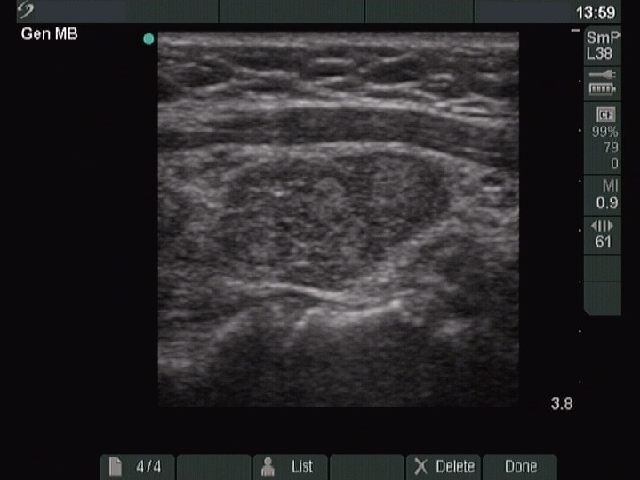

Ultrasonography. The two lobes differed in echo pattern. The right lobe (upper image) was echonormal and contained small hypoechogenic foci with an echogenicity index of less than 5% while the left lobe (lower images) was composed of a central hypoechogenic area surrounded with an echonormal rim, therefore it resembled a large hypoechogenic nodule comprising great proportion of the lobe . On the other hand the lesion had irregular borders and showed a heterogeneous pattern and similar smaller areas were found elsewhere in the lobe.

Cytological diagnosis: benign Hashimoto's thyroiditis.

Comment. The ultrasound pattern is remarkable, the left lobe highly resembles a pattern of a large hypoechogenic nodule. On thorough analysis of the images and the video, it seemed more likely that this area is not a nodule in a pathological sense but only more active focus of the underlying thyroiditis. The differentiation between a nodule in pathological sense and a hypoechogenic focus of Hashimoto's thyroiditis is not always possible, even in this case it not fully unequivocal.